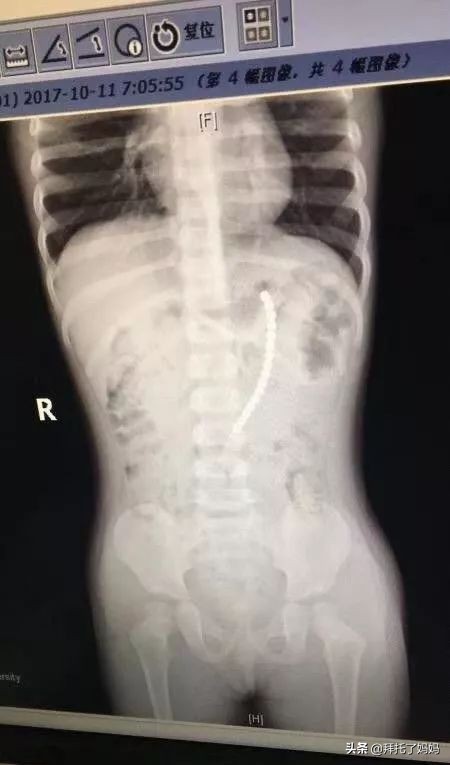

复旦大学附属儿科医院医生给这个小女娃拍了片子,结果,人们惊呆了!

一共有19颗珠子在体内!!

复旦大学附属儿科医院副院长、儿外科专家郑珊团队,给孩子做了胃镜,取出了胃里的六颗巴克球,但发现有一排珠子已经穿出胃壁,到外面去了。

在腹腔镜下发现

剩余的珠子一颗连一颗构成一串

一端在胃里,另一端在小肠里

也就是说

孩子肠子和胃里面

都被巴克球穿孔了!

医生取出珠子后

再把小女娃的胃和小肠补上

万幸的是,这个2岁女孩吞珠后还算送医及时。郑珊教授介绍,巴克球一旦造成胃壁或是肠壁损伤,形成漏洞,就意味着大便等可能会漏到腹腔,导致腹膜炎甚至引发休克。